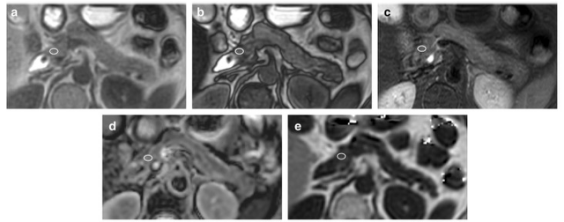

圖 66 歲女性,胰腺正常組脂肪肝。 感興趣區(qū)域 (ROI) 的測量在胰腺頭部進行軸位同相位成像 (a)、軸位反相位成像 (b)、軸位 T2 加權(quán)成像 (T2WI) (c)、軸位表觀擴散系數(shù) (ADC) 圖 (d) 和軸向多回波 3D DIXON (e)